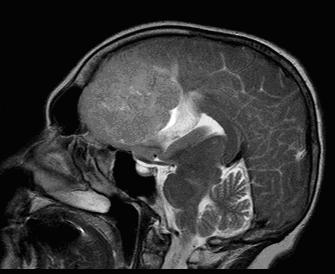

Beteg P. 38 év. Panaszok meredek csökkenése látás. A sagittalis MR kép (1.5T) a sella jelenlétét mutatta ki a nagy tumor vérzések - macroadenoma hipofízis. A beteg sikeresen működött, ott van a vizuális funkció helyreállítása.